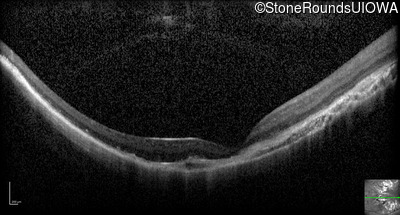

Optical Coherence Tomography - Left - 5/160

Exemplar / OCT Stack